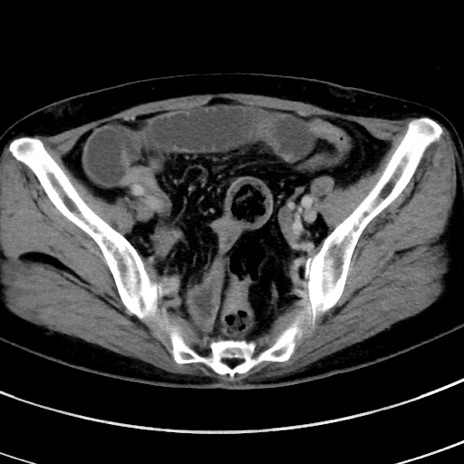

冠状断像

【症例】 60歳代女性

【主訴】むかつき、みぞおちの痛み

【現病歴】3日前よりむかつきがあり、食事がとれない。

【既往歴】糖尿病

【身体所見】発熱なし、心窩部圧痛軽度あるも、腹膜刺激症状なし。

【データ】WBC 7400、CRP 1.92